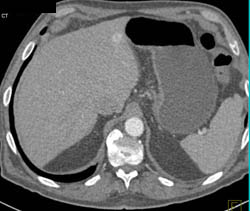

Diagnosis

Linitis Plastica